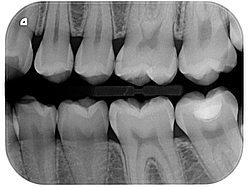

Digital Xrays

Using a small sensor placed briefly in the mouth, an x-ray image of high analysis is obtained.

This sensor functions as a miniature camera that is more sensitive to the radiation of the radiographic apparatus with respect to the normal light.